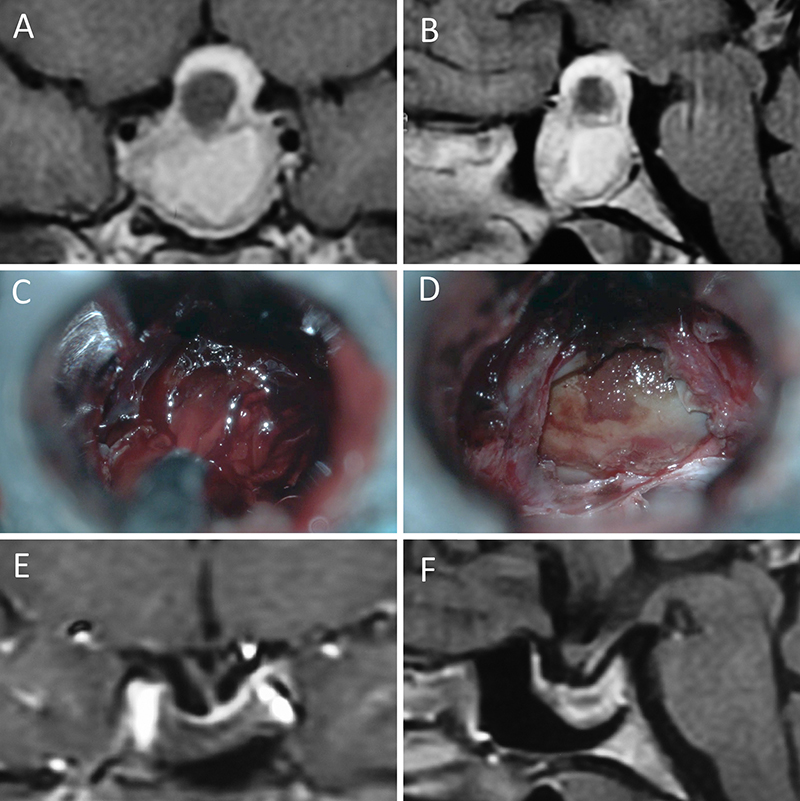

Figura 1: Macroadenoma no funcionante en mujer de 65 año s. Se decidió la cirugía tras evidenciarse crecimiento en los controles. Evolucionó favorablemente desde el punto de vista clínico-radiológico. A-B: RM preoperatoria; C-D: intraoperatorio; E-F: RM postoperatoria.

Figura 2: Macroadenoma no funcionante en mujer de 31 años. La paciente presentó en el preoperatorio déficit visual que mejoró tras la cirugía. A-B: RM preoperatoria; C-D: intraoperatorio; E-F: RM postoperatoria.

Figura 3: Macroadenoma no funcionante en un hombre de 64 años. El paciente presentó en el preoperatorio déficit visual que mejoró tras la cirugía. A-B: RM preoperatoria; C-D: intraoperatorio; E-F: RM postoperatoria.